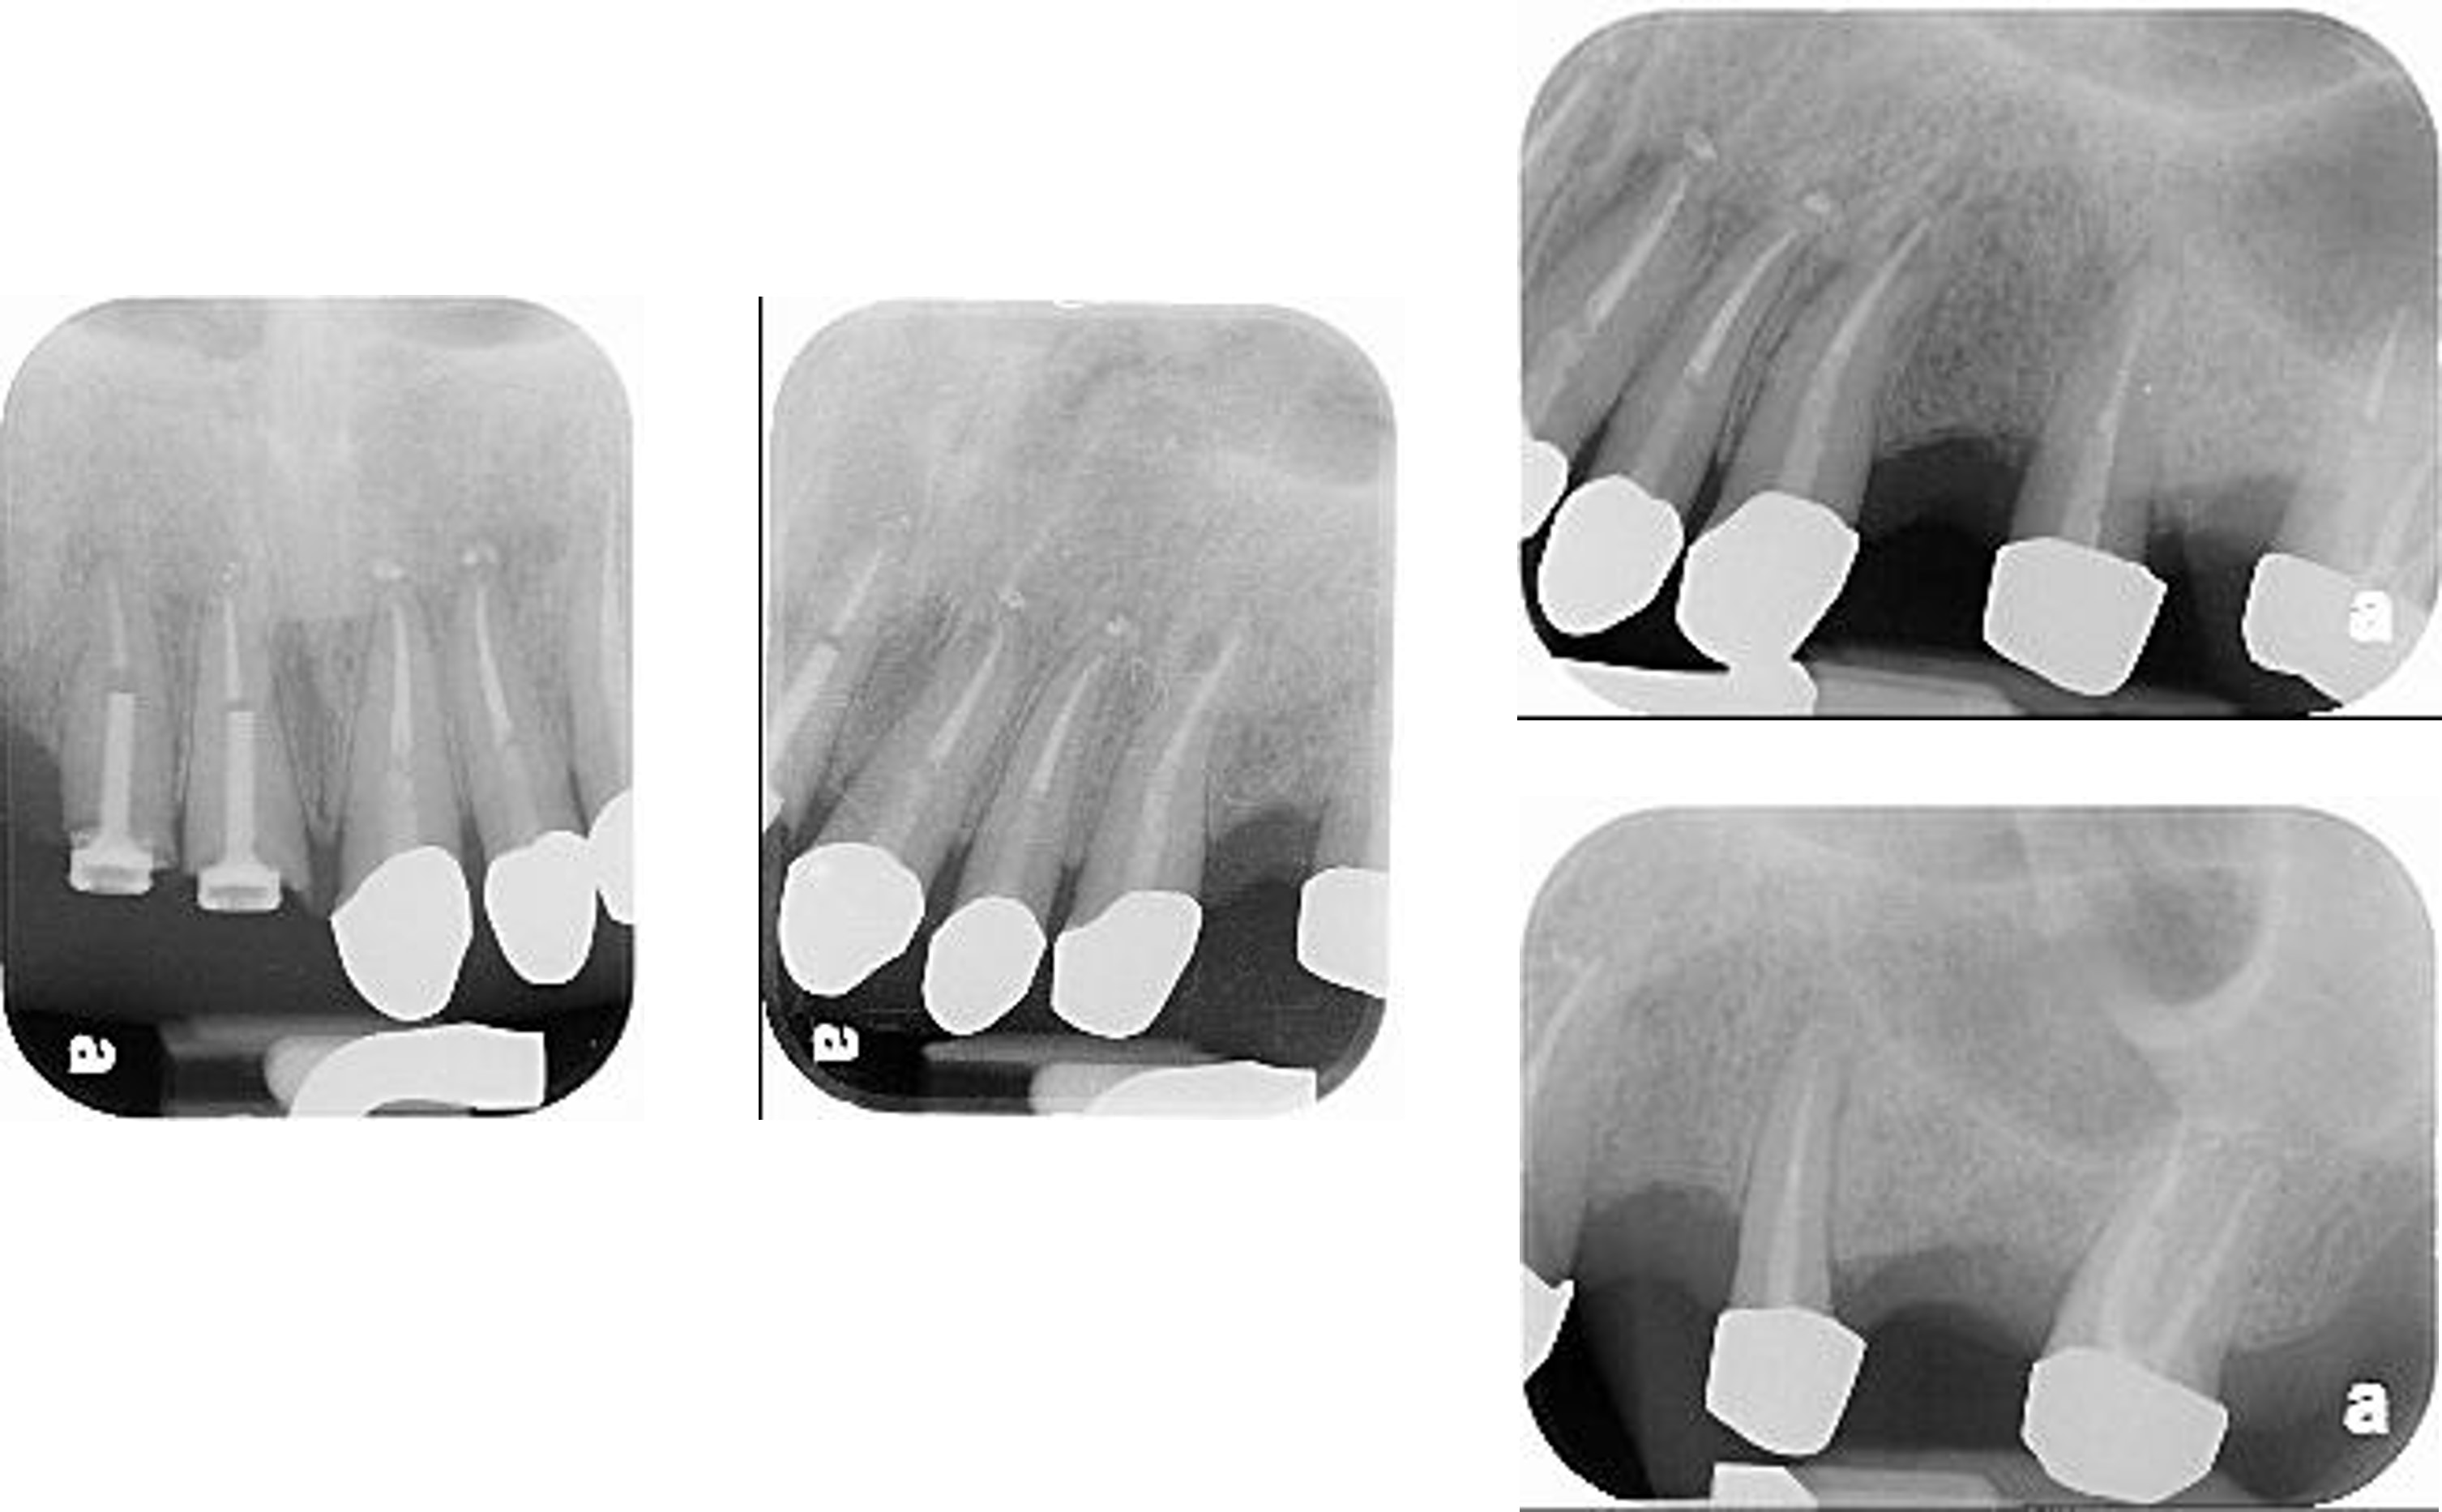

術後X光片

術前、術後比較